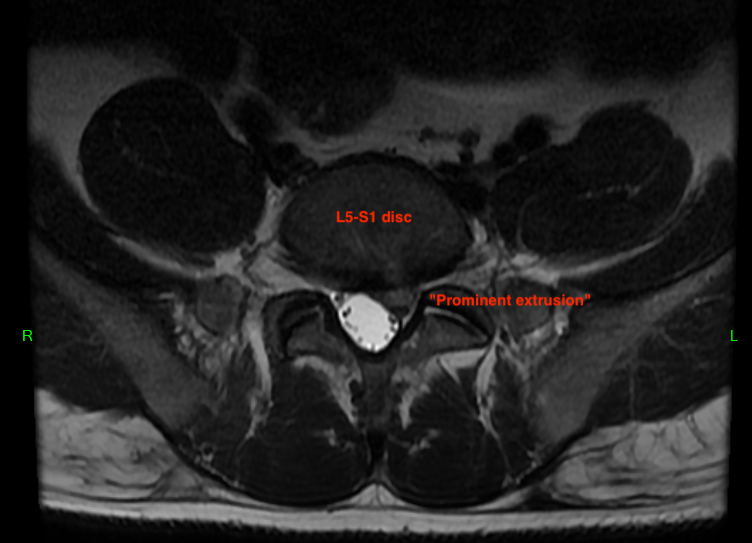

Last, observe my L5-S1 disc. The "S" stands for sacral, and in adults, the sacrum is a triangle shaped bone at the base of the spine. The individual bones (S1, S2, etc.) all fuse together when we are teenagers so the IVDs between them become irrelevant. Notice how my paracentral (off-centered) herniation interferes with the thecal sac (fortunately, there's plenty of space, so my cauda equina has not been crushed) and also the S1 transiting nerve root. This nerve root exits through the thecal sac then continues downward through the sacrum where another pair of foraminal openings exist. As soon as the S1 nerve root exits the thecal sac, it gets compressed by the disc extrusion. Many other nerves within the thecal sac are anatomically displaced as well, although I did not have any associated pain or neurological dysfunction.

(L5-S1 Axial MRI)